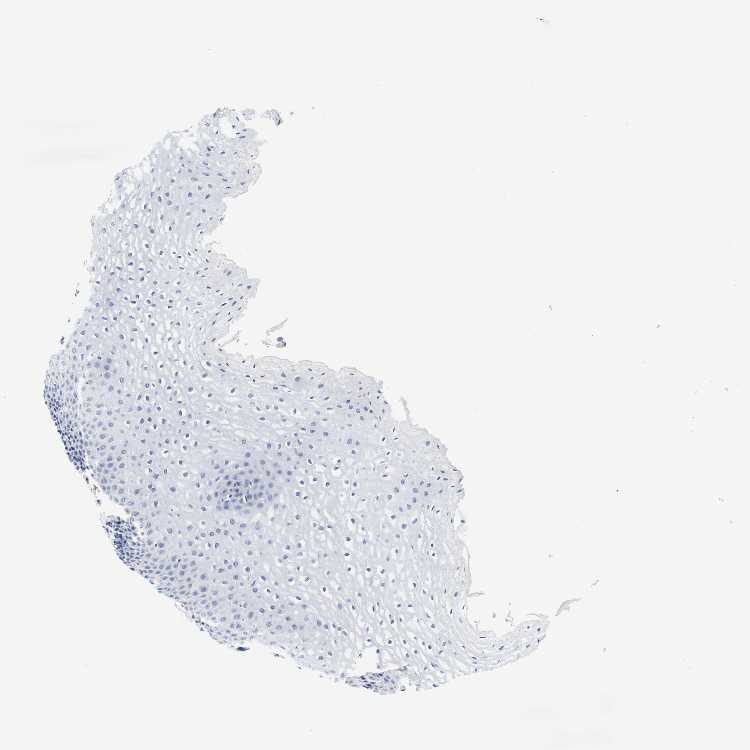

ESOPHAGUS - HPA RNA-seqi

The RNA-seq details section shows detailed information about the individual samples used for the transcript profiling and results of the RNA-seq analysis.

Information about each individual sample is listed below, including gender, age, a tissue section image and estimated fractions of cell types. nTPM (normalized transcripts per million) values give a quantification of the gene abundance which is comparable between different genes and samples.

Female, age 70

Esophagus sample 130

nTPM: 0.2

Cell types%

Squamous epithelial cells:

35

Smooth muscle cells:

15

Skeletal muscle cells:

5

Other cell types:

45